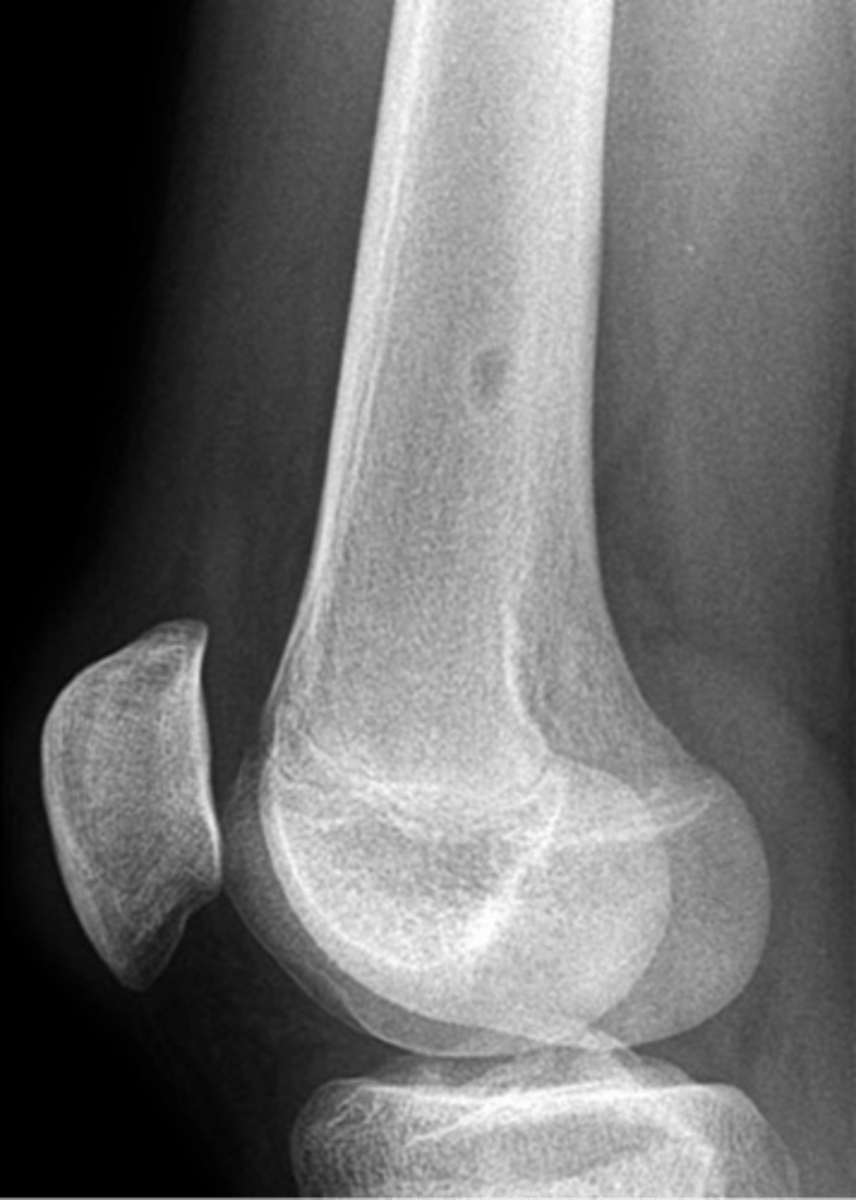

Geographic bone blister

ID radiographic feature of non-ossifying fibroma indicated by top arrow

<p>ID radiographic feature of non-ossifying fibroma indicated by top arrow</p>

Septations

ID radiographic feature of non-ossifying fibroma indicated by bottom arrow

<p>ID radiographic feature of non-ossifying fibroma indicated by bottom arrow</p>

Pathologic fracture

Non-ossifying fibroma with _____

<p>Non-ossifying fibroma with _____</p>